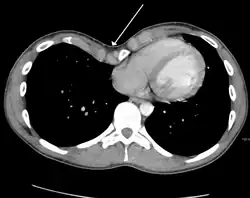

Many scales have been developed to determine the degree of deformity in the chest wall. Most of these are variants on the distance between the sternum and the spine. One such index is the Backer ratio which grades the severity of deformity based on the ratio between the diameter of the vertebral body nearest to xiphosternal junction and the distance between the xiphosternal junction and the nearest vertebral body.[20] More recently the Haller index has been used based on CT scan measurements. An index over 3.25 is often defined as severe.[21] The Haller index is the ratio between the horizontal distance of the inside of the ribcage and the shortest distance between the vertebrae and sternum.[22]

Chest x-rays are also useful in the diagnosis. The chest x-ray in pectus excavatum can show an opacity in the right lung area that can be mistaken for an infiltrate (such as that seen with pneumonia).[23] Some studies also suggest that the Haller index can be calculated based on chest x-ray as opposed to CT scanning in individuals who have no limitation in their function.[24]

Pectus excavatum requires no corrective procedures in mild cases.[25] Treatment of severe cases can involve either invasive or non-invasive techniques or a combination of both. Before an operation proceeds, several tests are usually performed. These include, but are not limited to, a CT scan, pulmonary function tests, and cardiology exams (such as auscultation and ECGs).[26] After a CT scan is taken, the Haller index is measured. The patient's Haller is calculated by obtaining the ratio of the transverse diameter (the horizontal distance of the inside of the ribcage) and the anteroposterior diameter (the shortest distance between the vertebrae and sternum).[27] A Haller Index of greater than 3.25 is generally considered severe, while normal chest has an index of 2.5.[22][28][29] The cardiopulmonary tests are used to determine the lung capacity and to check for heart murmurs.[30]